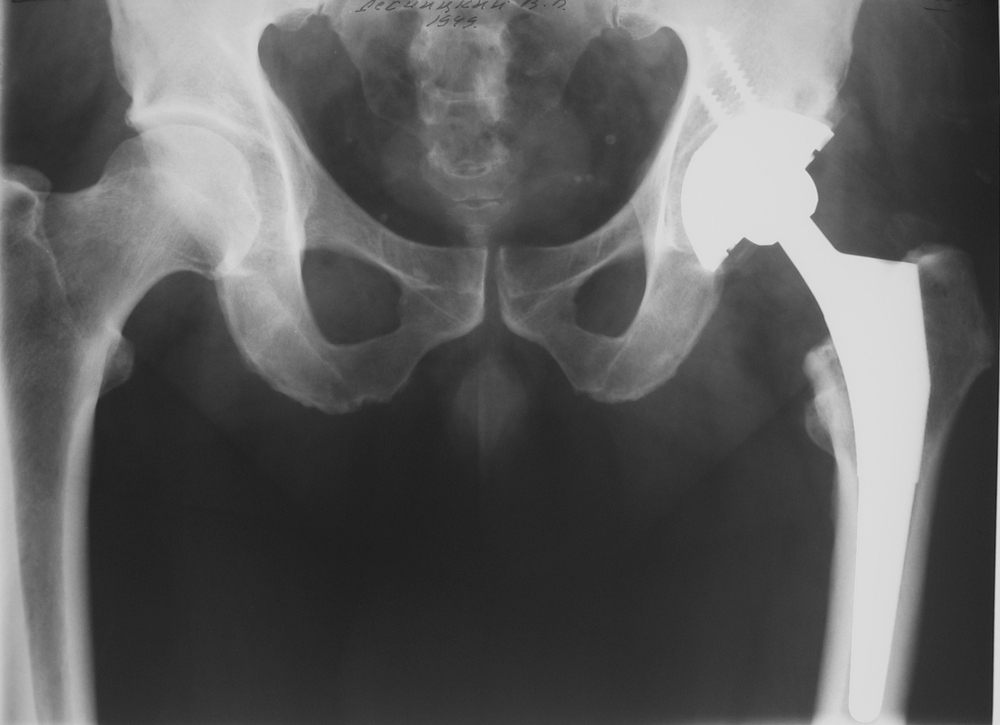

Да лет 25 тому назад, родился менее здоровым, чем хотелось бы, вот недавно понадобилось сделать такую операцию... боли были жуткие, сейчас иду на поправку)_ месяц и буду уже ходить, а может и бегать на своих 2их